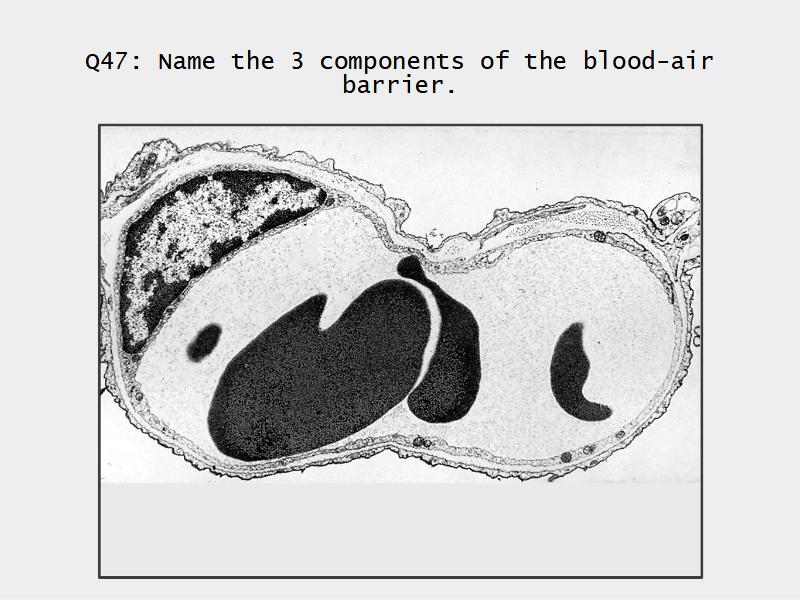

What cells are present?

Components of the Blood-Air Barrier?

What other barrier systems are found in the body?

What are the purpose of each of these barrier systems? Connected with physiology will unlock the pathology.

Barriers

- Blood-air